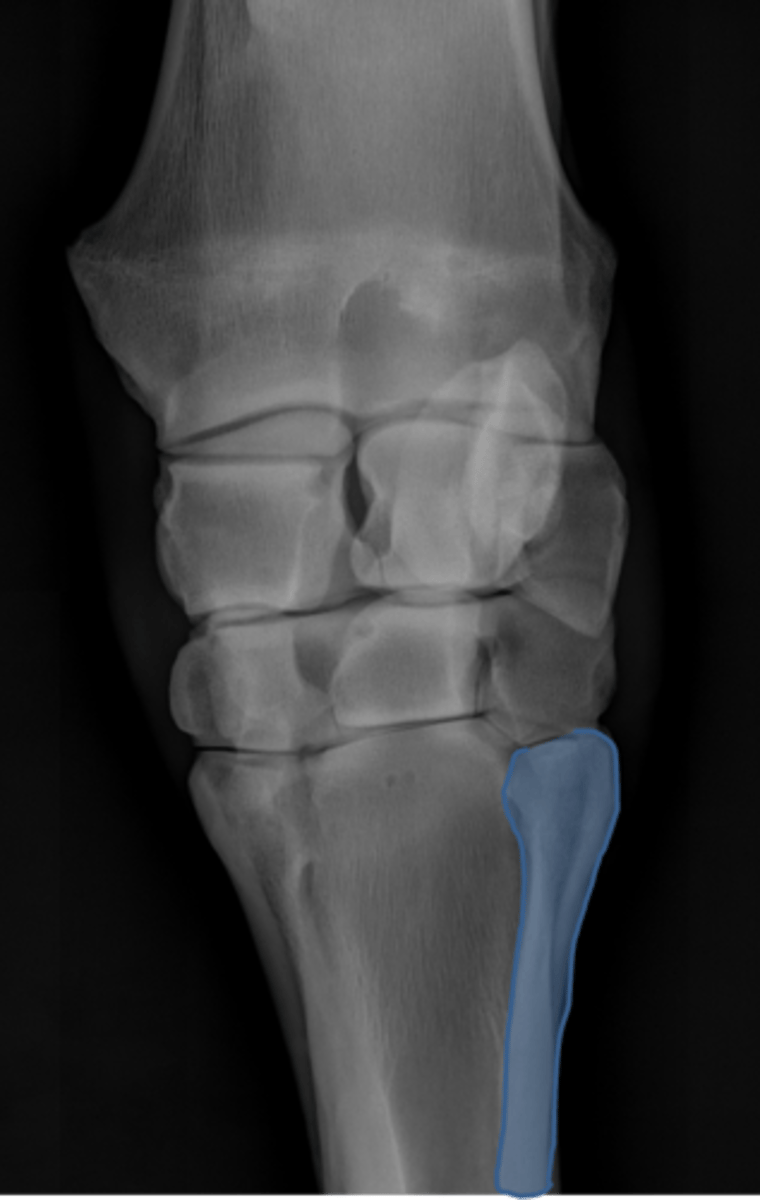

DLPMO

ID view of carpus

Accessory carpal bone

Radial carpal bone

Intermediate carpal bone

Ulnar carpal bone

Second carpal bone

Third carpal bone

Fourth carpal bone